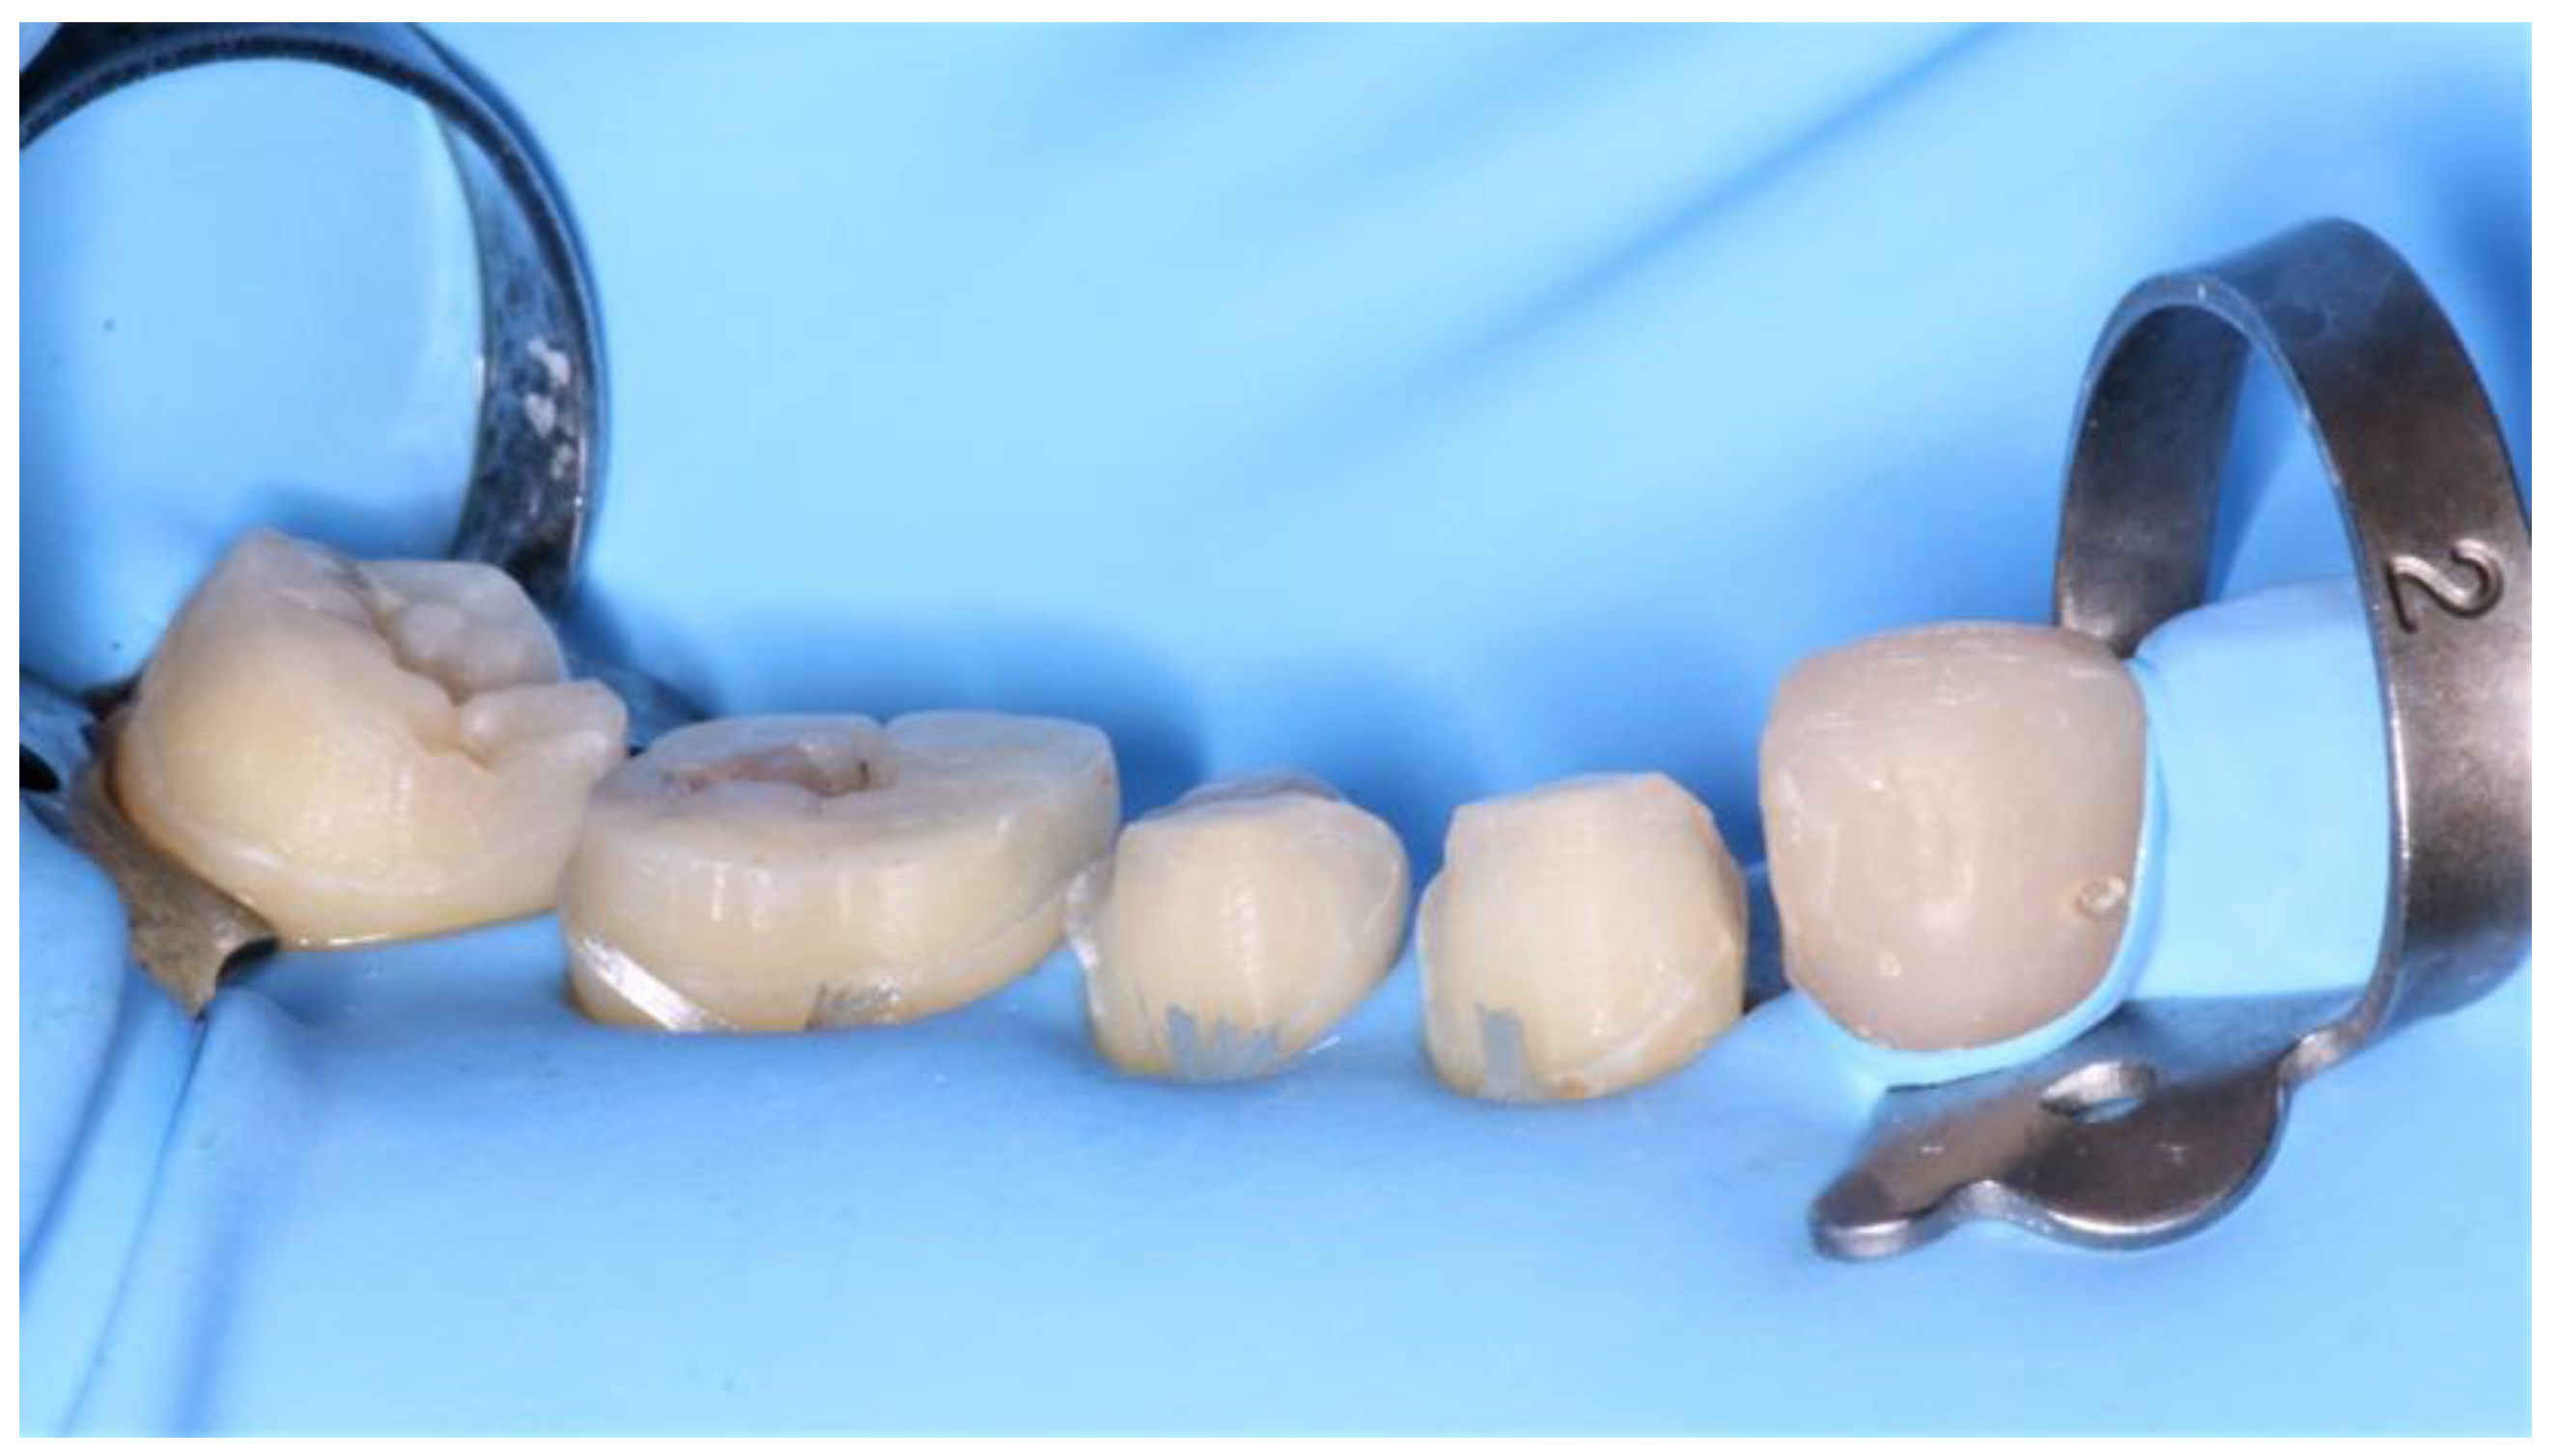

During the second clinical session, the temporary resin was applied, the teeth were thoroughly cleaned, and the fixed prosthetic components (Figure 11) were tried on.

Figure 11.

Fixed prosthetic elements traditionally glazed and polished.

Once validated, a rubber dam was installed (Figure 12) to allow optimal bonding according to the protocol described above (Figure 13).

Figure 12.

Installation of a rubber dam.